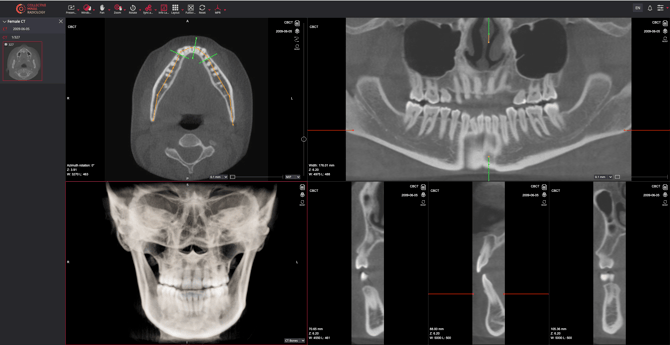

For efficient image manipulation in dental radiology, consider using the following tools when reviewing CBCT images

- Select the menu tool

MPR > Dental MPR

Curved MPR tool

Scrolling Along the Teeth

- Click and drag the middle green reference line on the curved line in the top-left viewport.

Adjusting the Field of View

- Extend or minimize the green line to enlarge or reduce the field of view.